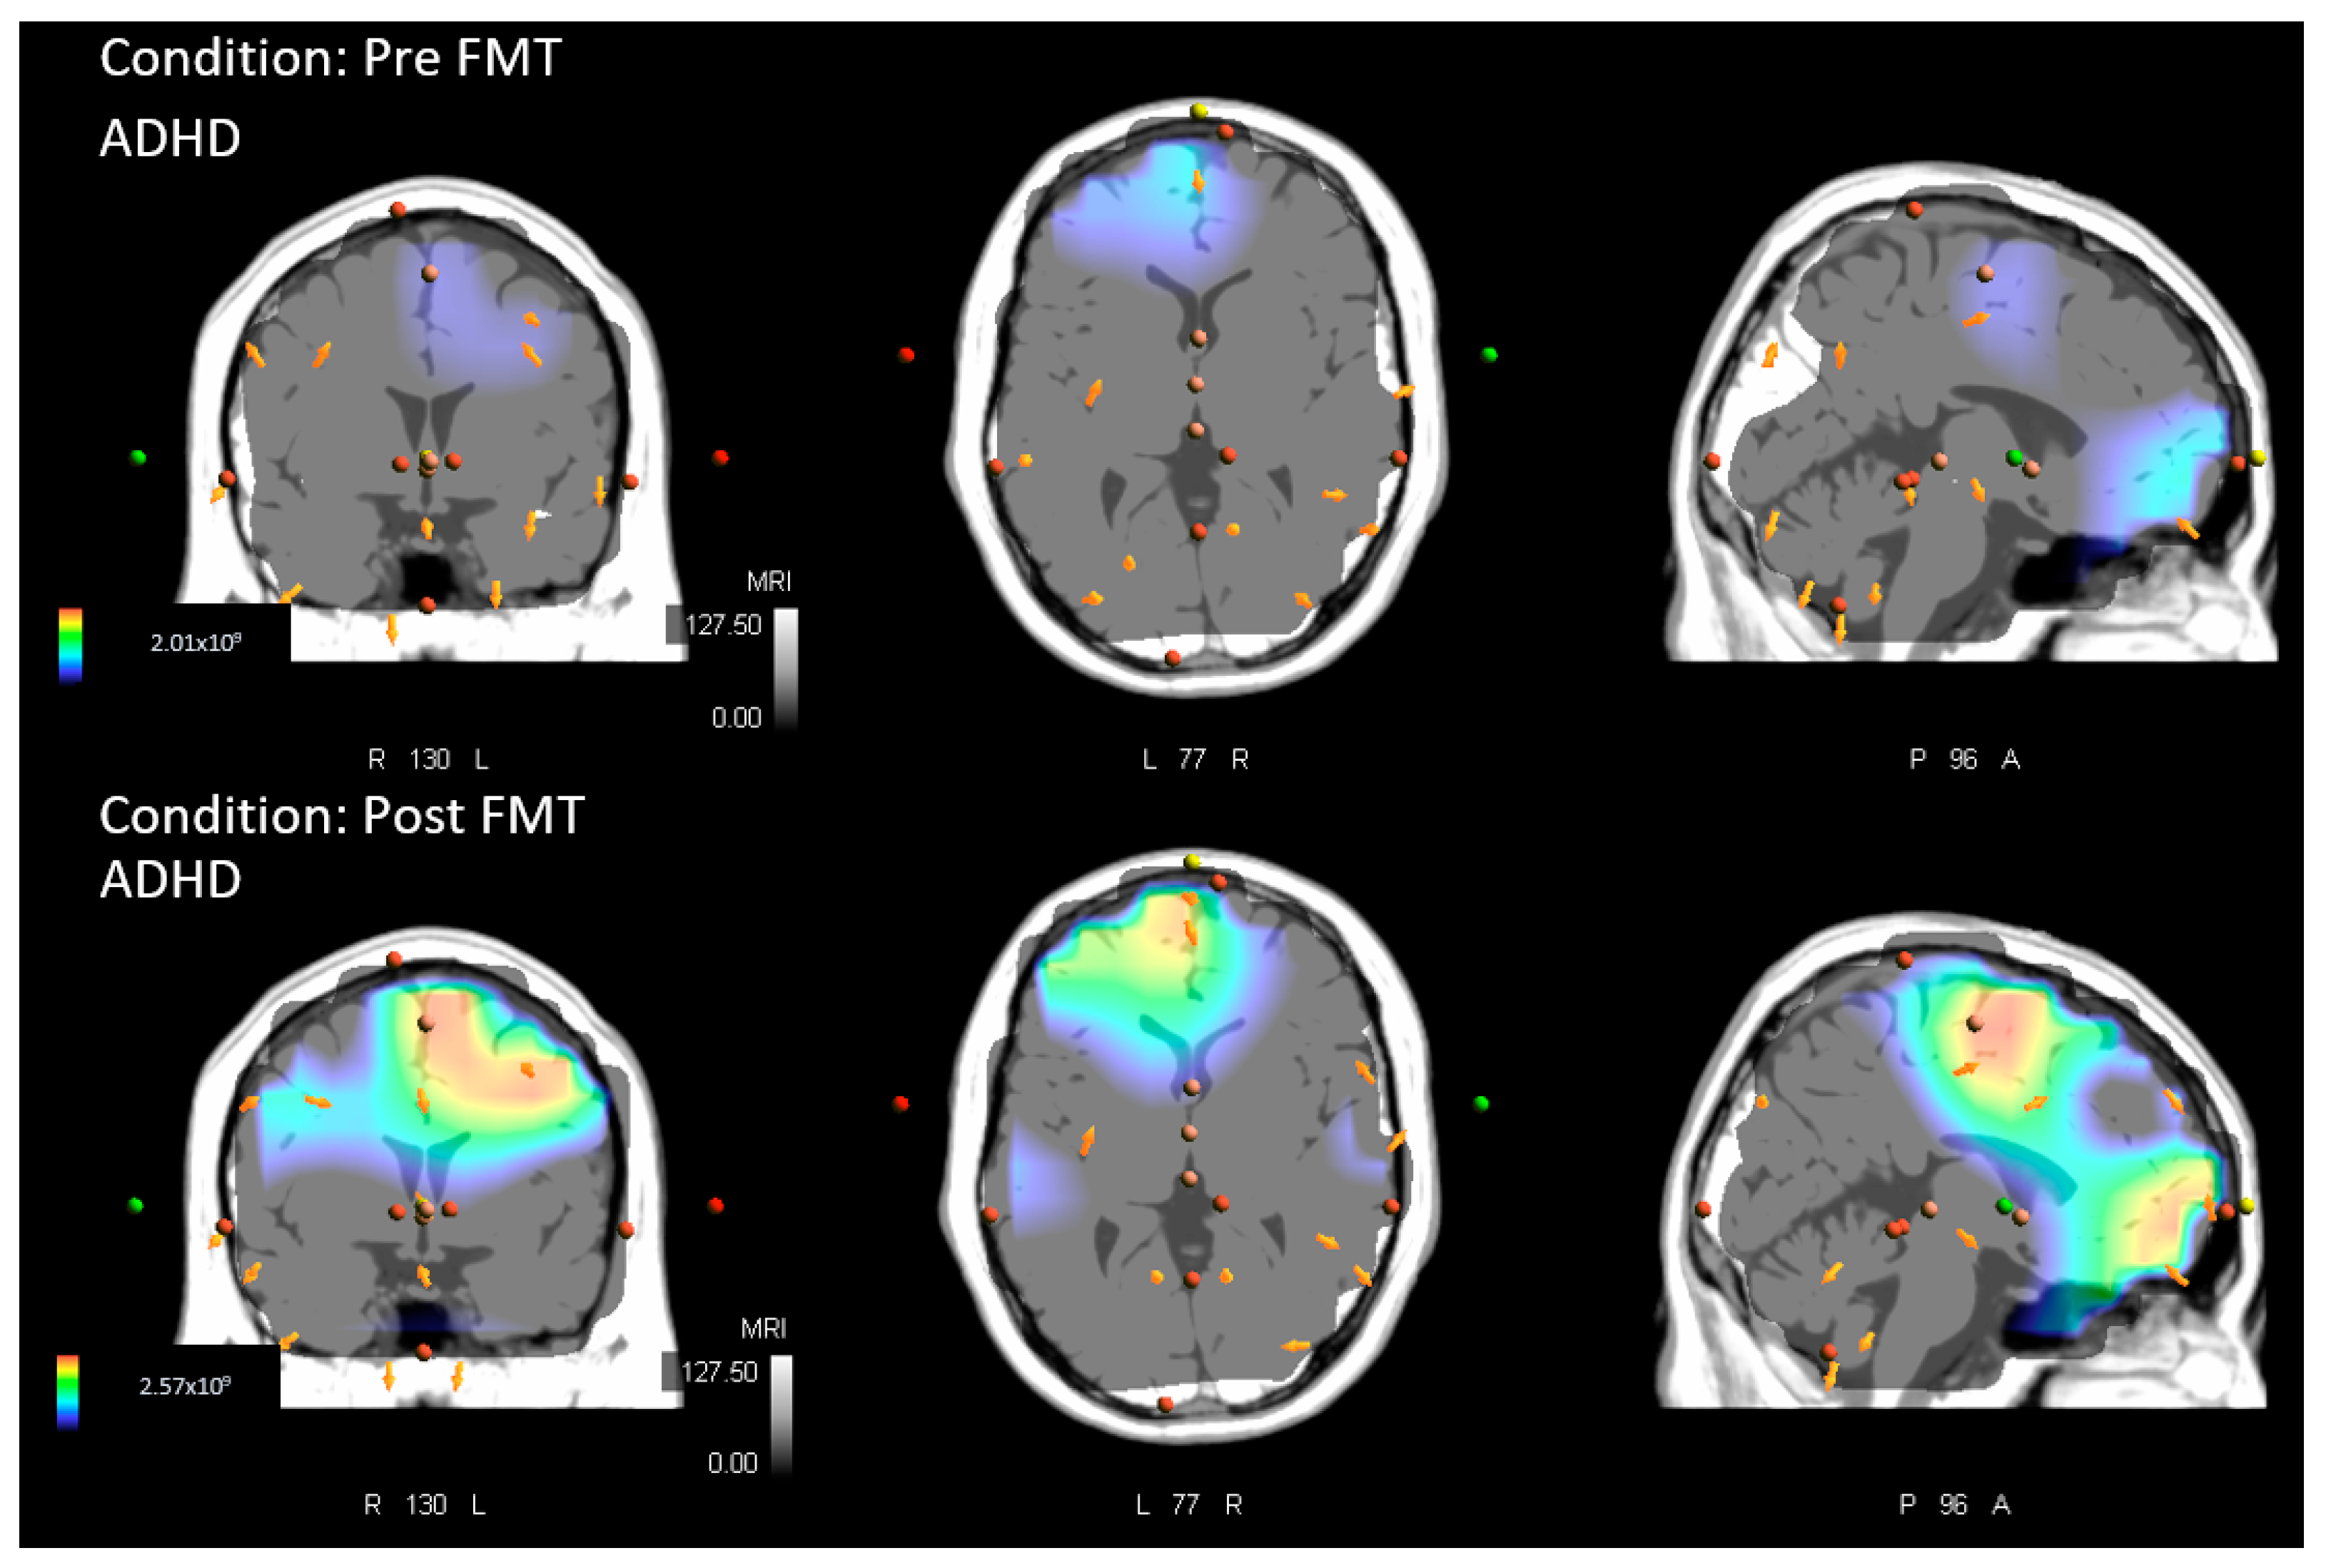

Novel Force-Matching Task (FMT) Parameters

2.4.2. Source Localization–sLORETA Analysis

- Within groups (pre-measures vs. post-measures) for both the ADHD and control group. Similarly, comparisons were performed for both tasks, the MTT and FMT. This comparison was performed to assess whether locations of source activity differed within each group after acquisition of either of the motor paradigms.- ADHD baseline vs. ADHD post.